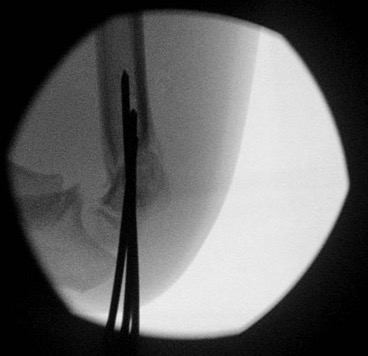

Closed reduction and K wire technique

Set up

On arm table

Sterile tourniquet available should open reduction be required

Manipulation technique (must have adequate reduction, or very unstable and cannot K wire)

1. Consider milking any soft tissues that may be trapped (pucker sign)

2. In-line traction at 30o

- 2 minutes to overcome soft tissues

- check fluoroscopy

3. Reduce translation / rotation / varus and valgus

- adjust carrying angle / Baumann's angle

- avoid medial impaction / cubitus varus

- supination - maximise the traction on the lateral ligments to disimpact lateral side

- pronation - maximise traction on the medial ligaments to disimpact medial side

4. Flexion pushing olecranon forward with thumb

- shoot through AP to assess reduction

- check Baumann's angle

- check medial and lateral columns with oblique views

5. Hand position (point thumb towards side of impaction)

- posteromedial displacement - hyperpronation in flexion

- posterolateral displacement - hypersupination in flexion

6. Check lateral image

- lock elbow in flexion and rotation

- externally rotate the shoulder

- ensure that the anterior humeral line is correct

- reduction of teardrop on lateral

- may need to increase the flexion

2 x lateral K wires

Technique

- hold elbow in flexion

- place K wire into lateral condyle

- place other index finger on the humerus to guide aim

- 2 x lateral 1.6 mm K wires (consider 2 mm K wires in larger children)

- one K wire on the direct lateral surface, just lateral to the capitellum

- one on the capitellar surface